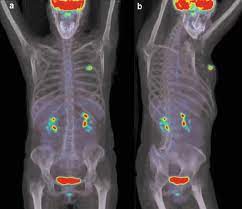

Do Ct Scan Detect Breast Cancer / Woman Receiving Medical Scan Breast Cancer Stock Photo Edit Now 1097370935 / During the study, the diagnostician can change the thickness of the cut up to 1 mm.. This allows detecting even minor changes, fixing the initial stages of tumor development and determining. This lung cancer awareness month learn how future processing is able to detect lung cancer from ct scans with the help of ai. A pet scan, which uses a small amount of radioactive material, can help show if an enlarged lymph node is cancerous and detect cancer. In some cases, physicians use all three imaging techniques. It can also show changes caused by other medical conditions.

Ct Vs Mri What S The Difference And How Do Doctors Choose Which Imaging Method To Use Memorial Sloan Kettering Cancer Center from www.mskcc.org These techniques include ct scans, mri scans and radioisotope scans. Some risks associated with ct scans include: The whole appointment can take up to an hour and a half depending on which part of your body they are scanning. Cost of ct of mammary glands in usa. Mri scan and contrast enhancement. This lung cancer awareness month learn how future processing is able to detect lung cancer from ct scans with the help of ai. Computed tomography (ct or cat) scan. Bone scans, positron emission tomography (pet), and computed tomography (ct) all continue to be employed alone or in combination for the detection of breast cancers suspected to have spread.

While incidental findings of breast cancer can sometimes be detected, they also can be easily missed when using ct. This test may reveal whether breast cancer has spread to the bone. Staging and treatment of breast cancer. Early detection and diagnosis of cancer can significantly increase your chances of being treated successfully. Computed tomography (ct or cat) scan. Ct scans are most often done as an outpatient procedure. Drugs may be injected directly into the arteries. Breast cancer is the most common female cancer in the united states, the second most common cause of cancer death in women (after lung cancer), and the leading. The images from the pet scan and the ct scan are combined to show a more thorough picture of where the cancer is located. Ct scans can detect bone and joint problems, like complex bone fractures and tumors. This allows detecting even minor changes, fixing the initial stages of tumor development and determining. During a breast mri , you lie on your stomach on a padded scanning table. Learn more about cat scans today.

A ct scan can show whether breast cancer has spread to the lungs or liver. Ct scans and cat scans describe the same imaging test. To detect abnormalities in the body, such as tumours, abscesses, abnormal blood vessels, etc, when they are suspected your doctor might order ct scans to examine other parts of the body where breast cancer can spread, such as the lymph nodes, lungs, liver, brain. A radiographer operates the scanner. Learn more about cat scans today.

Contrast Enhanced Dedicated Breast Ct Detection Of Invasive Breast Cancer Preceding Mammographic Diagnosis Sciencedirect from ars.els-cdn.com What science says about ct scans and cancer. Ct scans and cat scans describe the same imaging test. Your doctor might order ct scans to examine other parts of the body where breast cancer can spread, such as the lymph nodes, lungs, liver, brain, and/or spine. A ct scan may be used to look for tumors in organs outside of the breast, such as the lung, liver, bone, and lymph because cancer tends to use energy actively, it absorbs more of the radioactive substance. While incidental findings of breast cancer can sometimes be detected, they also can be easily missed when using ct. A radiographer operates the scanner. During the study, the diagnostician can change the thickness of the cut up to 1 mm. A scanner then detects this substance to produce.

Thermography is another option and can be an excellent source of very early detection for not only breast abnormalities, but. A ct scan is one of the most frequently utilized exams to detect cancer and to show things such as a tumor's shape and size. Ct scans can detect bone and joint problems, like complex bone fractures and tumors. How can we treat cancer? Bone scans, positron emission tomography (pet), and computed tomography (ct) all continue to be employed alone or in combination for the detection of breast cancers suspected to have spread. It's also important to follow recommended screening guidelines, which can help detect certain cancers early. We prefer to scan from bottom to top, because if a patient. During a breast mri , you lie on your stomach on a padded scanning table. Learn more about cat scans today. Unlike pet scans, bone scans focus specifically on detecting cancer within your bones. Some risks associated with ct scans include: A ct scan (also called a cat scan or computed tomography scan) can help doctors find cancer and show things like a tumor's shape and size. A ct scan can show whether breast cancer has spread to the lungs or liver.

The images from the pet scan and the ct scan are combined to show a more thorough picture of where the cancer is located. Staging and treatment of breast cancer. The pet scanner detects signals that are given off from the tracer. For example, ct has become a useful screening tool for detecting possible tumors or lesions within the abdomen. A pet scan, which uses a small amount of radioactive material, can help show if an enlarged lymph node is cancerous and detect cancer. This provides a series of images from many different angles. It's also important to follow recommended screening guidelines, which can help detect certain cancers early. A scanner then detects this substance to produce. Computed tomography (ct or cat) scan. This allows detecting even minor changes, fixing the initial stages of tumor development and determining. The whole appointment can take up to an hour and a half depending on which part of your body they are scanning. How can we treat cancer? This combination scan is called a pet/ct.